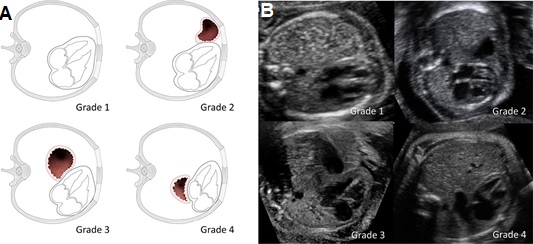

5.3 Vị trí dạ dày

Đánh giá vị trí dạ dày gần đây đã được đưa vào như một phương pháp gián tiếp để đánh giá mức độ nghiêm trọng của bệnh trong CDH bên trái. Nếu dạ dày còn ở trong bụng thì có tiên lượng tốt hơn dạ dày nằm trong lồng ngực. Gần đây Cordier và cộng sự đã khẳng định vị trí của dạ dày giúp tiên đoán tỷ lệ sống còn sau sinh [7]. Một số nghiên cứu khác cũng khẳng định vị trí của dạ dày có liên quan rõ với tỷ lệ tử vong sơ sinh, sự cần thiết của ECMO và tình trạng suy hô hấp của trẻ ngay sau sinh. Vị trí của dạ dày trong lồng ngực có tương quan với tỷ lệ tử vong và bệnh tật sau sinh và độc lập với o/e LHR [11].

Vị trí của dạ dày được phân độ như sau:

- Độ 1 hoặc bụng: dạ dày ở vị trí bình thường do đó không được nhìn thấy trong lồng ngực

- Độ 2 hoặc phía trước trái trong lồng ngực: dạ dày được nhìn thấy ở phía trước đỉnh tim, tiếp xúc với thành trước ngực

- Độ 3 hoặc từ giữa đến sau ngực trái: dạ dày không tiếp xúc với thành trước ngực trái; tuy nằm cạnh van nhĩ thất nhưng với phần lớn hơn của nó vẫn ở phía trước

- Độ 4 hoặc sau tim: hầu hết dạ dày nằm sau van nhĩ thất, bên cạnh tâm nhĩ trái của tim ở trong lồng ngực phải

Hình 8. Hình vẽ phác họa (A) và hình ảnh siêu âm (B) của thai nhi có CDH bên trái và vị trí dạ dày khác nhau. Độ 1: Dạ dày không thấy trong lồng ngực. Độ 2: Dạ dày tiếp xúc với thành ngực trước. Độ 3: Dạ dày cạnh van nhĩ thất nhưng vẫn chiếm ưu thế phía trước. Độ 4: Hầu hết dạ dày nằm sau van nhĩ thất.[7]